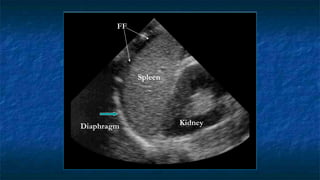

4)FAST: LUQ exam

 Evaluating

 Spleno-renal interface

 Possibility of fluid in splenorenal recess

and presplenic /subphrenic space( most

common space for fluid collection in

LUQ)

FF

Kidney

Spleen

Diaphragm